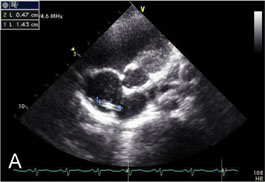

Fig. 1-A

Remained TIVD with vegetation within RA after TIVD removal operation on echocardiogram

Fig. 1-A Remained TIVD with vegetation within RA after TIVD removal operation on echocardiogram